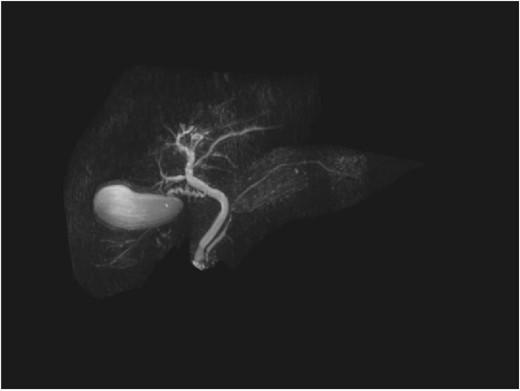

A man in his 70s presented to the emergency department with painless obstructive jaundice with dark urine and pale stools. The patient denied having any fever, nausea, vomiting, or weight loss. Liver function test progressively worsened during the admission peaking at a bilirubin of 287 umol/L (normal 2–20), alkaline phosphatase 694 U/L (normal 30–110), and alanine aminotransferase 160 U/L (normal < 40). Initial assessment on computed tomography and ultrasound raised concerns for primary pancreatic head neoplasm or cholangiocarcinoma (Fig. 1). He subsequently underwent magnetic resonance cholangiopancreatography (MRCP), which showed involvement of the entire common bile duct with no definite stricture or dilatation and no discrete pancreatic head mass (Fig. 2). Positron emission tomography showed abnormal uptake in the intrahepatic and extrahepatic bile ducts, focal uptake in the tail of the pancreas, and lymph nodes in the porta hepatis, retroperitoneum, and right iliac fossa (Fig. 3). Tumour markers revealed a carbohydrate antigen 19-9 (CA19-9) of 3286 kU/L (normal < 34).

CT scan showing thickening and enhancement of the entire extrahepatic common bile duct with intrahepatic duct dilatation.